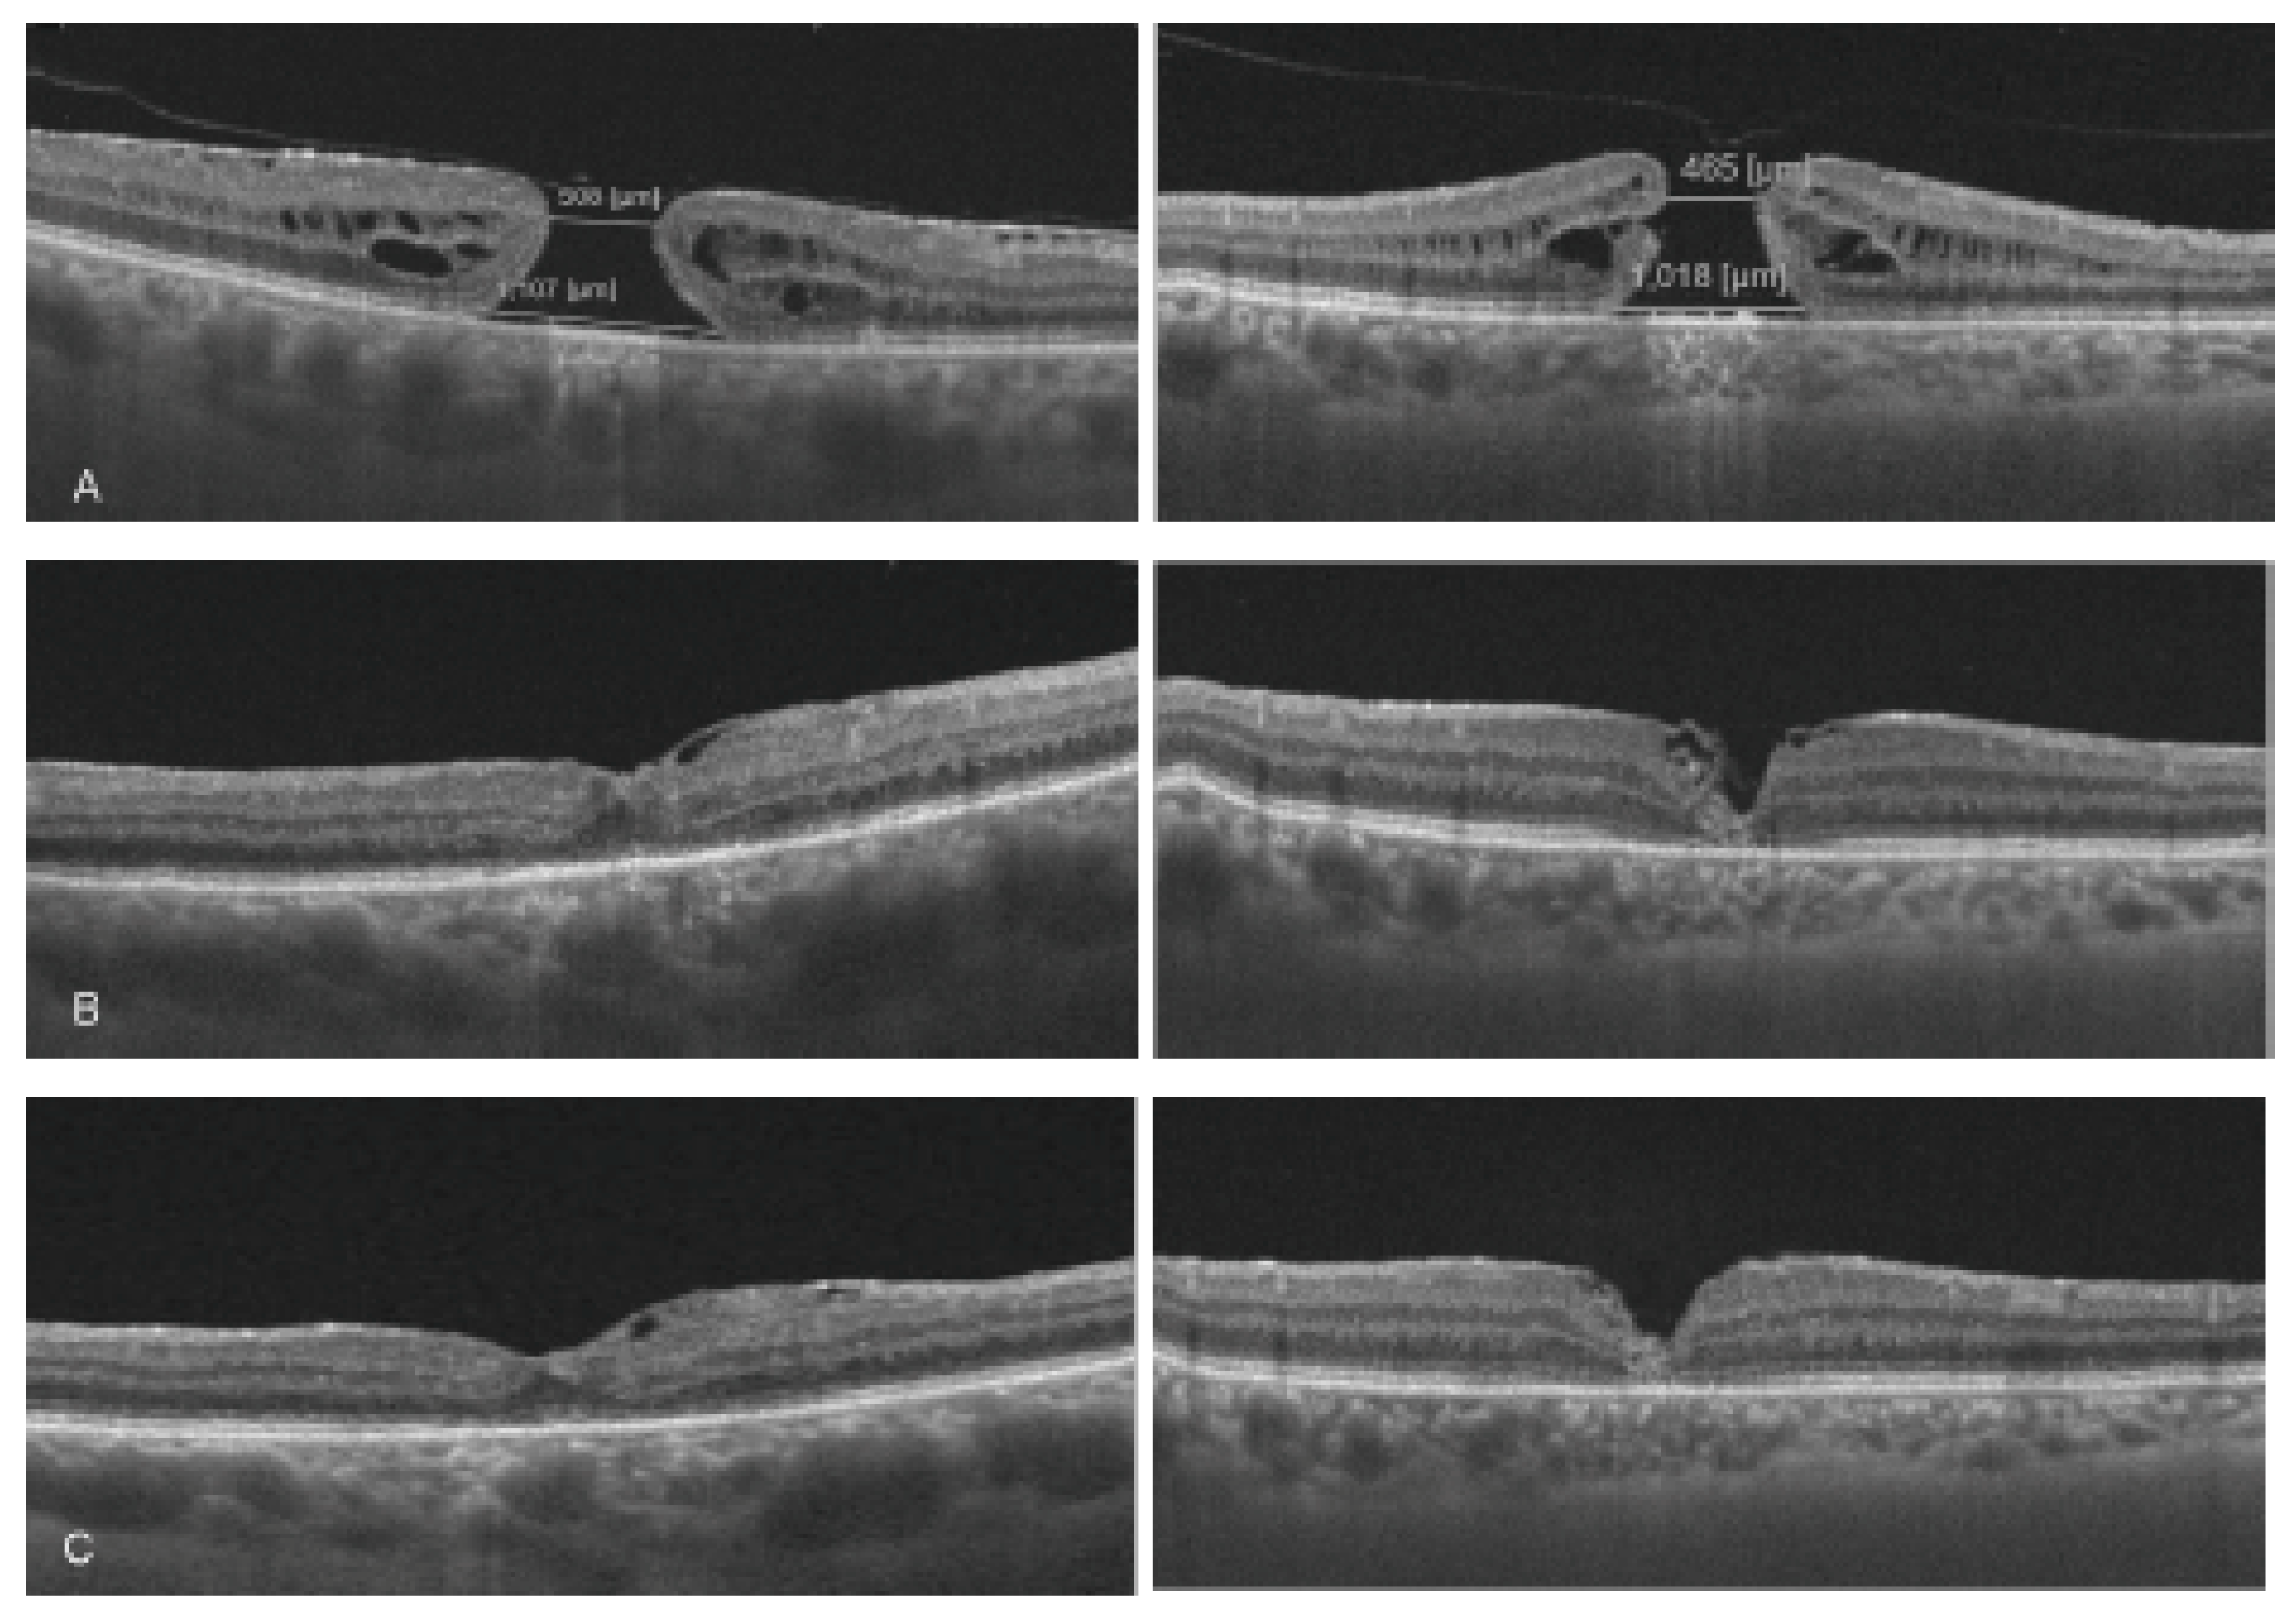

medicina free full text infracyanine green vs brilliant blue g in inverted flap surgery for large macular holes a long term swept source oct analysis html

contractility of temporal inverted internal limiting membrane flap after vitrectomy for macular hole scientific reports